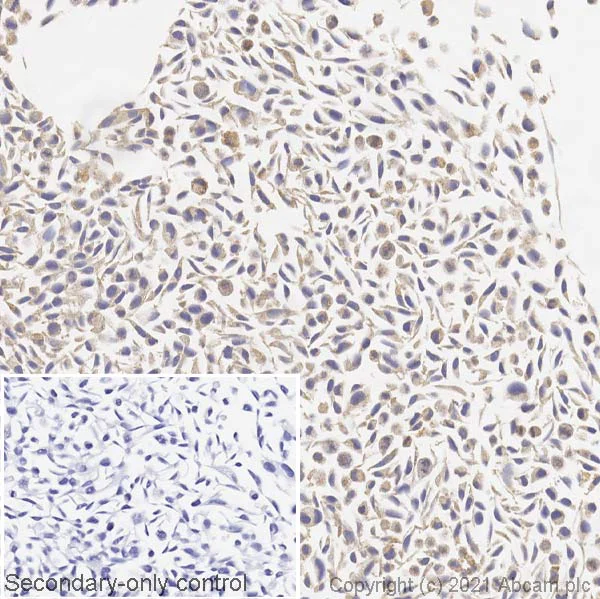

Immunohistochemistry (Formalin/PFA-fixed paraffin-embedded sections) - Anti-BRAF (mutated V600E) antibody [VE1] (AB228461)

IHC image of BRAF (mutated V600E) staining in a section of formalin-fixed paraffin-embedded A375 cell line (carrying mutant BRAF V600E) performed on a Leica BOND™ system using the standard protocol. The section was pre-treated using heat mediated antigen retrieval with sodium citrate buffer (pH6 epitope retrieval solution 1) for 20mins. The section was then incubated with ab228461 at 5ug/ml for 15 mins at room temperature and detected using an HRP conjugated compact polymer system. DAB was used as the chromogen. The section was then counterstained with haematoxylin and mounted with DPX. The inset secondary-only control image is taken from an identical assay without primary antibody.

This image was generated in-house using a previous batch manufactured using hybridoma production method.